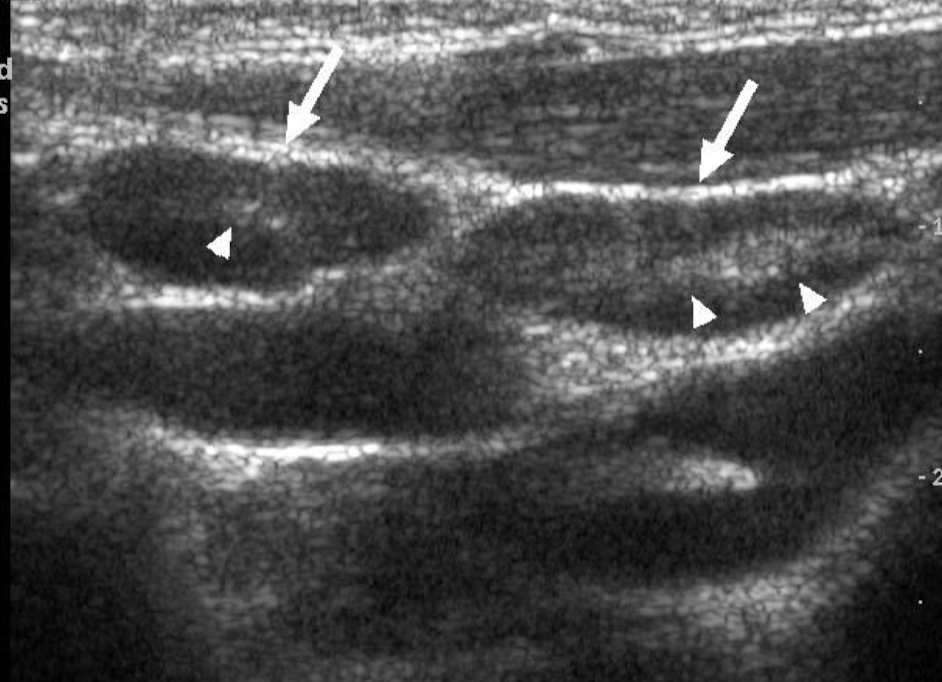

USG

lo mejor, primer recurso

ganglio homogeneo hipoecoico

se preserva forma e hilio hiperecoico: benigno

hipervascularidad

perdida de la morfologia: maligno